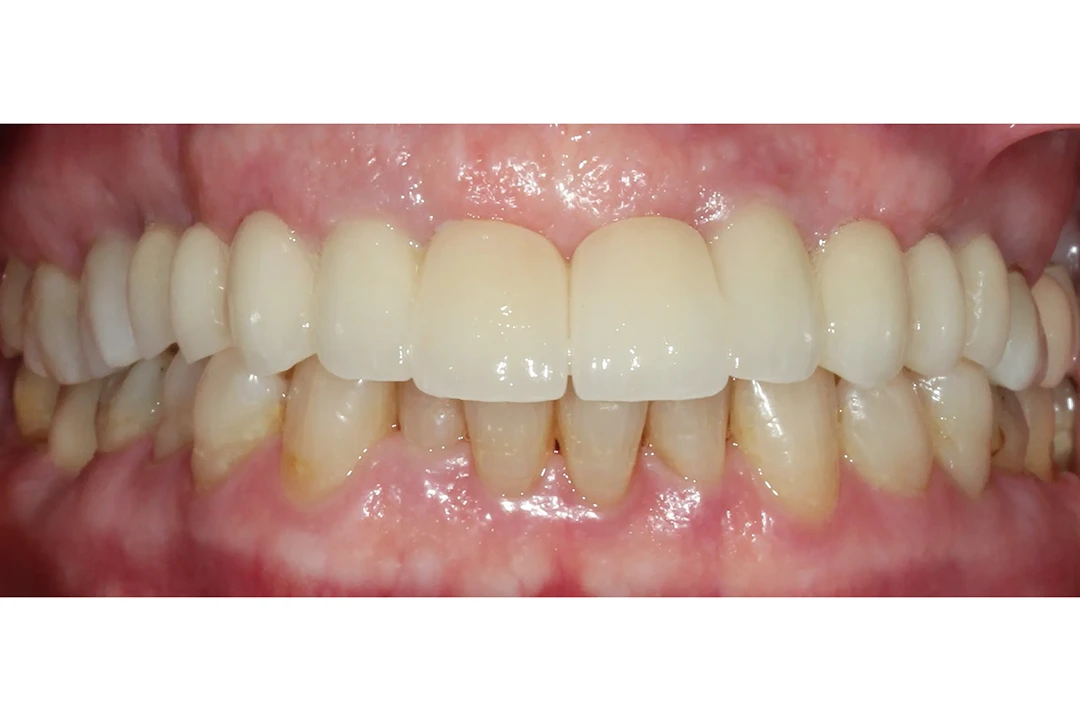

Paciente de 60 años, sufría porque sus dientes se movían y temía perderlos todos, pero gracias a la cirugía guiada y la técnica de carga inmediata, en un solo día Merche recuperó una sonrisa fija y natural. Volvió a comer, hablar y sonreír con mayor comodidad desde el primer momento.